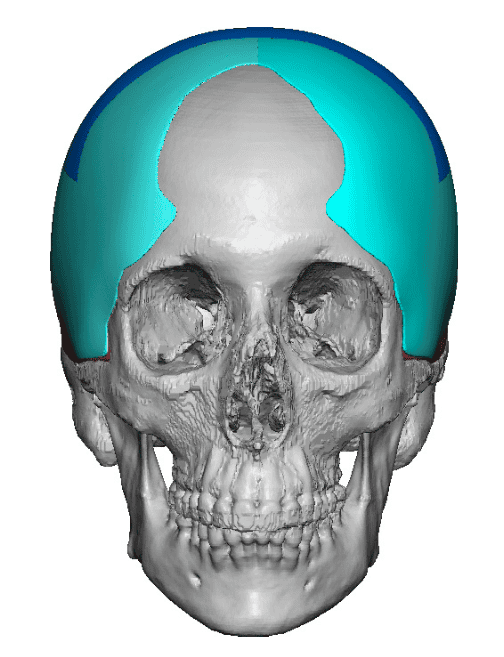

Severe narrowing skull deformity from prior sagittal craniosynostosis repair as an adult.

Complete replacement of entire skull by a custom implant with temporal fat injections.

Severe narrowing skull deformity from prior sagittal craniosynostosis repair as an adult.

Complete replacement of entire skull by a custom implant with temporal fat injections.